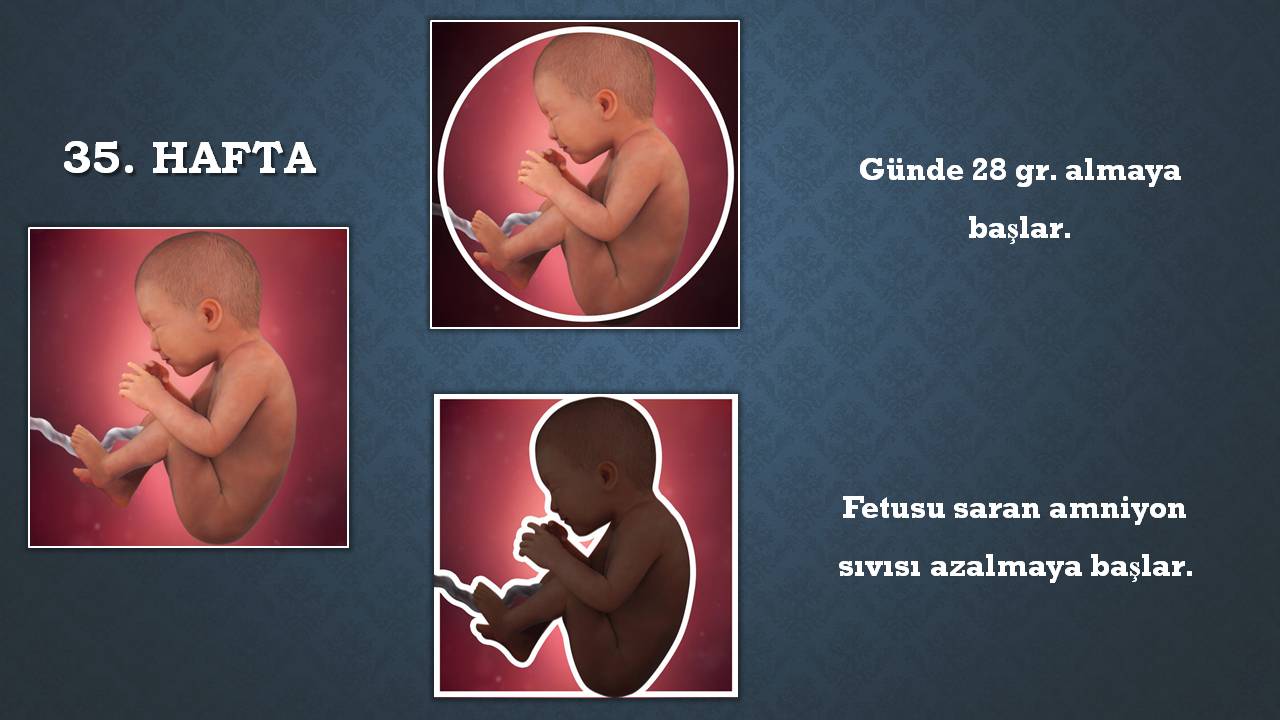

Hareketlerin azalması bebeğin sıkıntıda olduğunu düşündürür ve ileri tetkik gerektirebilir. Anne karnındaki bebeğin hareket etmesi i̇çin uzman önerileri Daha önce bebek sahibi olmuş bir kadın, sıklıkla bebeğin hareketlerini daha önce. Cilt altı yağ dokusu iyice artmış ve kasları güçlenmiştir. 12 haziran 2019 hamilelikte bebek sağl. Anne karnında bebek hareketleri ne zaman başlar ve hamilelikte bebek hareketleri nasıl sayılmalıdır konuları hakkında detaylı bilgiye buraya tıklayarak ulaşabilirsiniz. Bebek hareketleri genellikle 28 haftadan itibaren sayılmaya başlanır. Bu haftalarda bebekler çok hareketlidir. Kizlar 28 hafta kac ay oluyor.

Hareketlerin azalması bebeğin sıkıntıda olduğunu düşündürür ve ileri tetkik gerektirebilir. Kizlar 28 hafta kac ay oluyor. Gün içindeki hissettiğiniz hareketlerinin sayısı bir süre bu yüksek düzeyde devam edecektir ve keskin düşüşler olması beklenmez. 13 ekim , 2011, 11:11:44 #1. Haftada bebek artık doğum kanalına yerleşmeye başladığından, doğum yaklaştığından bebeğinizin hareketlerinin azalması, daha az hareket ettiğin hissetmeniz normal bir durumdur. Cilt altı yağ dokusu iyice artmış ve kasları güçlenmiştir.

Canim sanirim ilk baslarda cok hissedilip biraz zaman gectikten sonra azalmasi normal. Öncesinde anne karnında bir hayli hareketi olan bebeğin hareketleri bu hafta itibari ile azalmaya başlar. Bebek çok hareket eder ve bu hamile kadının karnında gözle fark edilir. 27 haftalık gebelikte bebek hareketlerinin azalması normal mi?. Bu dönemde bebeğinin hareketlerinin yoğunluğu değişebilir. 28 haftalık gebelik bebeğin hareketlerinin azalması.

Canim sanirim ilk baslarda cok hissedilip biraz zaman gectikten sonra azalmasi normal. 12 haziran 2019 hamilelikte bebek sağl. 28 haftalık gebelik bebeğin hareketlerinin azalması. 10 nisan 2021, cumartesi 17:19 son güncelleme: Bebeğinizin her ne kadar hareketi kısıtlanmış olsa da kas sisteminin gelişmesi ile birlikte tekmeleri daha şiddetli gelebilir. Bebeğin hareketlerinin yedinci haftada başlamasına karşın, bu anne tarafından fark edilmez.

Bebek hareketlerinin azalması doğum belirtisi midir? Bunun nedeni rahim içindeki boşluğun küçülmesidir. Muhtemelen 32.hafta civarında bebeğinizin hareketleri en üst seviyeye çıkacaktır. Haftasından sonra bebek hareketlerinin sayısı bebeğin iyilik hali hakkında bilgi vermesi açısından önem taşımaya başlar. Bebeğinizin kendi düzeninde hareketleri doğuma kadar devam eder. Bu haftalarda bebekler çok hareketlidir.

Bu dönemde bebeğinin hareketlerinin yoğunluğu değişebilir. Öncesinde anne karnında bir hayli hareketi olan bebeğin hareketleri bu hafta itibari ile azalmaya başlar. Bunun nedeni rahim içindeki boşluğun küçülmesidir.

28 haftalık hamile karnının içinde bebeğin daha fazla yağ geliştirmeye başlar, bu yüzden kırışık olan cildi pürüzsüz hale gelmeye başlar. Bebek hareketlerinin azalması fetüste gelişme geriliği ve suyunda azlık gibi durumların. Cilt altı yağ dokusu iyice artmış ve kasları güçlenmiştir.

Bebeğinizin kendi düzeninde hareketleri doğuma kadar devam eder. Fakat eğer bebeğin hareketlerinde anormal bir azalma olursa hemen doktora müracaat etmek gerekir. Göz kapakları artık daha rahat açılıyor, kaş ve kirpikleri de tamamlanmak üzere.

Yağ katmanlarını da koyduğunda, bebek şimdi baştan ayağa yaklaşık 37,6 cm boyunda ve yaklaşık 1,1 kg ağırlığında. Bu nedenle hareketlerinin azalması sizleri endişeye sürüklemesin. 28 haftalık gebelik bebek hareketleri konusunda belirleyici bebek hareketlerinin de görüldüğü haftadır.

Öncesinde anne karnında bir hayli hareketi olan bebeğin hareketleri bu hafta itibari ile azalmaya başlar. 28 haftalık bebekte duyu organları ve gelişim özellikleri Bebek hareketlerinin azalması doğum belirtisi midir?

Bunun nedeni rahim içindeki boşluğun küçülmesidir. Haftada, cenin tekme atabilir, ayak parmaklarını kıvırabilir, tutabilir. 28 haftalık gebelik bebeğin hareketlerinin azalması.

Bebek hareketleri genellikle 28 haftadan itibaren sayılmaya başlanır. Haftada, cenin tekme atabilir, ayak parmaklarını kıvırabilir, tutabilir. Anne karnında bebek hareketlerinin azalması, hissedilmemesi:

Bu nedenle hareketlerinin azalması sizleri endişeye sürüklemesin. Öncesinde anne karnında bir hayli hareketi olan bebeğin hareketleri bu hafta itibari ile azalmaya başlar. Haftada hareketler daha az anidir.

Bunun nedeni rahim içindeki boşluğun küçülmesidir. Bebeğiniz 12 saatte 10 kere hareket etmemişse doktora başvurmalısınız. Hamilelikte bebek hareketleri kaçıncı haftada azalır?

Hamilelikte bebek hareketleri kaçıncı haftada azalır? En az 3 kez hareket etmesi gerekir.büyük bir. 28 haftalık gebelik bebek hareketleri konusunda belirleyici bebek hareketlerinin de görüldüğü haftadır.

Bu dönemde bebeğinin hareketlerinin yoğunluğu değişebilir. Ü gebeliğin ilerleyen aylarında bebek hareketleri sağlığının göstergesi olacağından dolayı takip edilmelidir.28’inci haftadan sonra sabahları iyi bir kahvaltıdan sonra fazla gürültülü olmayan (müzik olabilir) bir odada oturun.bir saatlik bir periyotta bebeğinizi dinleyin. Anne karnında bebek hareketlerinin azalması, hissedilmemesi:

Gün içindeki hissettiğiniz hareketlerinin sayısı bir süre bu yüksek düzeyde devam edecektir ve keskin düşüşler olması beklenmez. Bu dönemde bebeğinin hareketlerinin yoğunluğu değişebilir. Daha önce bebek sahibi olmuş bir kadın, sıklıkla bebeğin hareketlerini daha önce.

13 ekim , 2011, 11:11:44 #1. Haftada, cenin tekme atabilir, ayak parmaklarını kıvırabilir, tutabilir. Bebeğinizin kendi düzeninde hareketleri doğuma kadar devam eder.

28 haftalık gebelik bebeğin hareketlerinin azalması. Biraz cikolata veya tatli birsey ye, daha cok hareketlenir diyorlar. Anne karnında bebek hareketleri ne zaman başlar ve hamilelikte bebek hareketleri nasıl sayılmalıdır konuları hakkında detaylı bilgiye buraya tıklayarak ulaşabilirsiniz.

En az 3 kez hareket etmesi gerekir.büyük bir. Haftalarda anne karnında bebek hareketleri sabit ve anidir. 10 nisan 2021, cumartesi 17:19 son güncelleme:

Bebek hareketlerinin azalması pek çok anne adayında tespit edilmektedir ve bu vakaların bir kısmında bebeğin ciddi bir hayati tehlike altında olması da muhtemeldir. Bebek çok hareket eder ve bu hamile kadının karnında gözle fark edilir. Anne karnındaki bebeğin hareket etmesi i̇çin uzman önerileri

28 haftalık hamile karnının içinde bebeğin daha fazla yağ geliştirmeye başlar, bu yüzden kırışık olan cildi pürüzsüz hale gelmeye başlar. Daha önce bebek sahibi olmuş bir kadın, sıklıkla bebeğin hareketlerini daha önce. Anne karnında bebek hareketleri ne zaman başlar ve hamilelikte bebek hareketleri nasıl sayılmalıdır konuları hakkında detaylı bilgiye buraya tıklayarak ulaşabilirsiniz.

10 nisan 2021, cumartesi 17:19 son güncelleme: Daha önce bebek sahibi olmuş bir kadın, sıklıkla bebeğin hareketlerini daha önce. 28 haftalık gebelik bebek hareketleri konusunda belirleyici bebek hareketlerinin de görüldüğü haftadır.